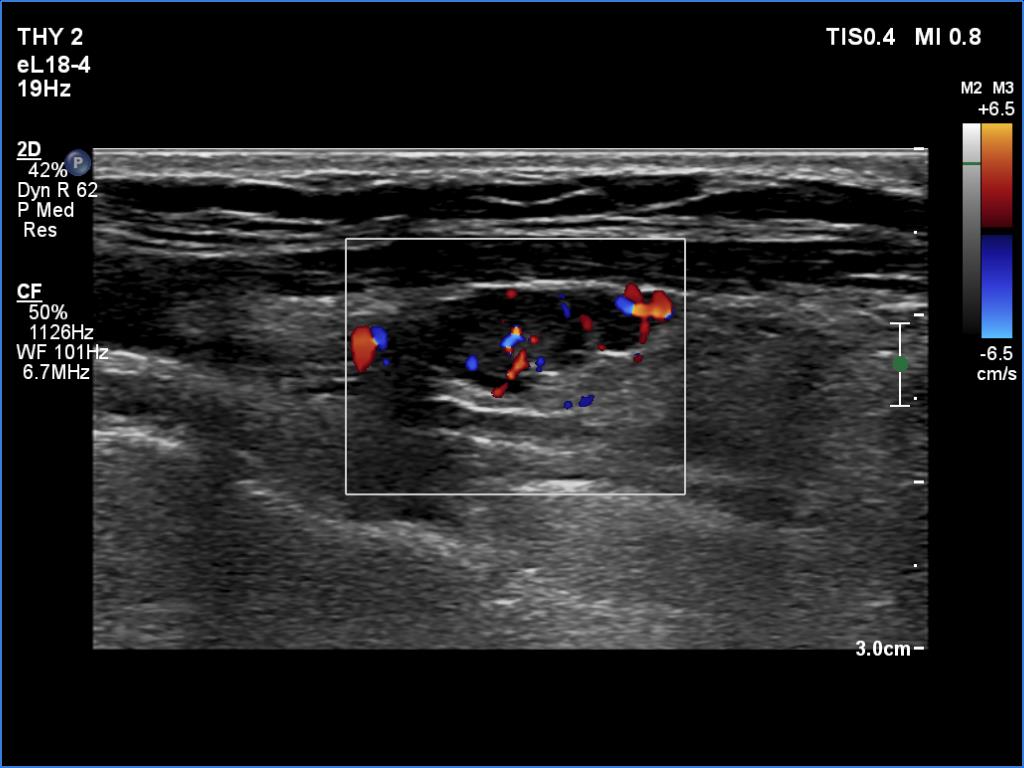

Ultrasonography. The right lobe was replaced with connective tissue. A hypoechoic mass was found in the left thyroid bed. On certain sections, this mass was very similar to a muscle fiber, however some other sections proved the presence of intralesional echogenic figures; the presence of back wall cystic figures was obvious but in the event of some granules microcalcifications should be considered. The lesion was vascularized, which excluded that the mass is muscle fiber.